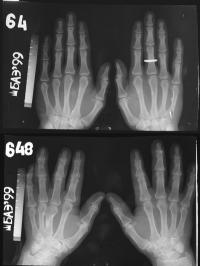

به گزارش شبکه‌ی خبری زیست‌شناسی (BNN)، محققان نشانگرهای زیستی جدیدی تولید کرده‌اند که طول عمر استخوان‌های بدن را تعیین می‌کند. این نشانگرها مشخص کرده‌اند روند پیر شدن افراد عمدتا تحت‌تأثیر ژنتیک آن‌ها است.

محققان دانشگاه تل‌آویو، استخوان‌های 400 خانواده‌ی روسی را بررسی کردند (787 مرد 18 تا 89 ساله و 723 زن 18 تا 90 ساله).

نتایج تحقیق مشخص کرد که مردان و زنان الگوهای پیری متفاوتی دارند:

- در مردان، ژن‌های بیان ‌شده با احتمال بیش‌تری روی سرعت پیری تاثیرگذار هستند.

- برای زنان ژن‌های بیان شده نشان می‌دهند در چه سنی تغییرهای قابل مشاهده روی استخوان‌ها دیده می‌شود.